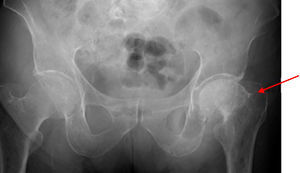

The PSA level was 4ng/mL, and the TSH level 1.56mIU/mL. A bone metabolism study revealed low vitamin D levels (25OHD D, 8.2ng/mL) with an iPTH level of 21pg/mL (NV, 15–65pg/mL). A complete blood count showed normocytic normochromic anemia, as well as leukopenia (3.870 WBCs). The erythrocyte sedimentation rate was 27mm. X-rays of the thoracic spine and the lumbar spine showed multiple vertebral fractures at T12 (grade 3), L1, L2, and L4 (grade 2). Bone densitometry showed a lumbar T score of −1.9 SD, −2.7 SD in total hip, and −0.6 SD in femoral neck, and bone scintigraphy revealed high uptake in T12, L1, L2, and L4 (Fig. 1).

During the study, the patient spontaneously reported pain and functional impotence in the left lower limb. Radiographic study was therefore completed, showing a previously unknown hip fracture and multiple lytic lesions in both femoral shafts (Fig. 2). The patient's course was complicated by respiratory tract infection and severe respiratory failure that did not respond to treatment and eventually caused death. Bone marrow puncture could not be performed.